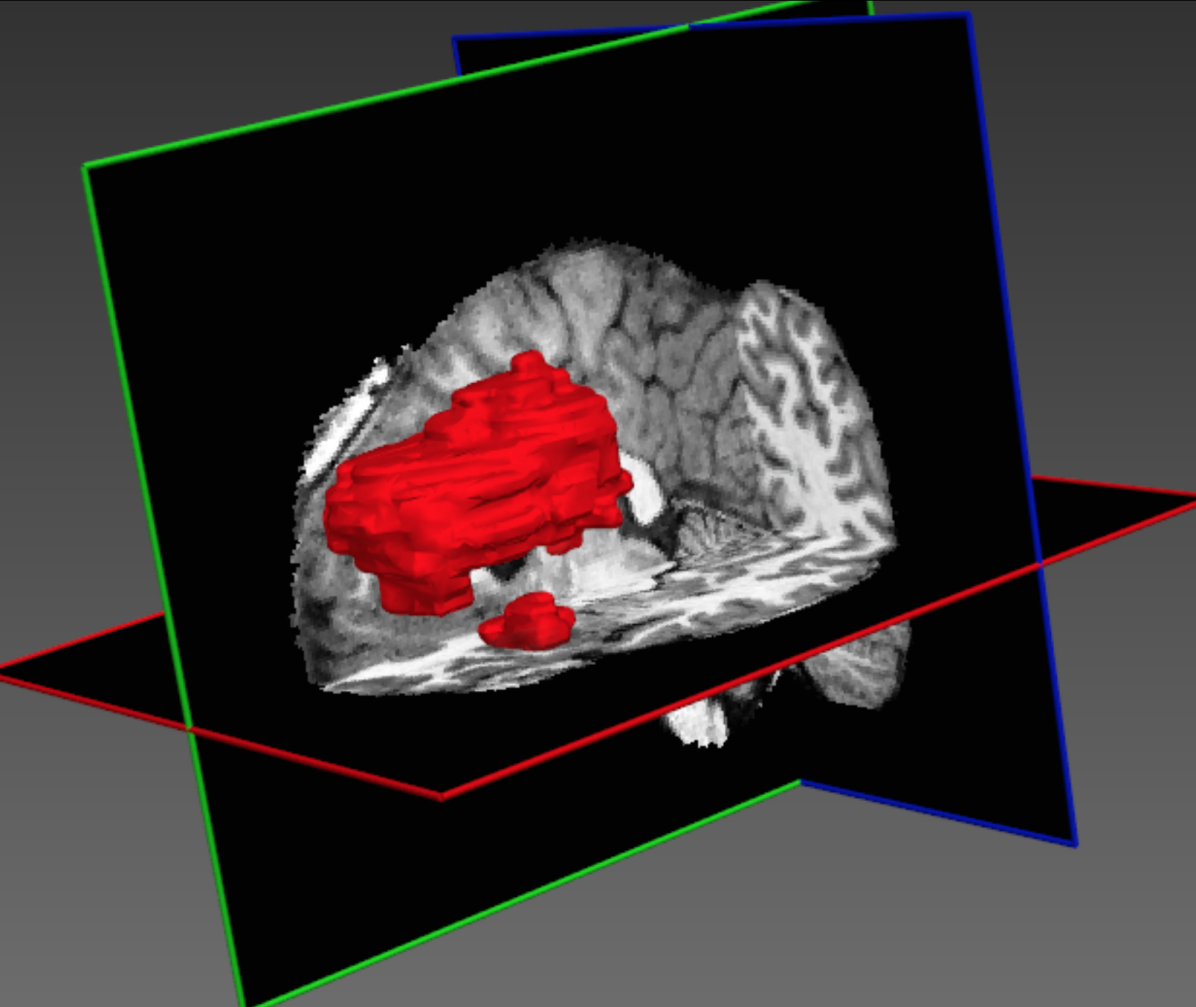

Figure 1 illustrates some of the challenges that arise when devising a computational approach for the task of automatic lesion segmentation. The figure summarizes statistics and shows examples of brain lesions in the case of TBI, but is representative of other pathologies such as brain tumors and ischemic stroke. Lesions can occur at multiple sites, with varying shapes and sizes, and their image intensity profiles largely overlap with non-affected, healthy parts of the brain or lesions which are not in the focus of interest. For example, stroke and MS lesions have a similar hyper-intense appearance in FLAIR sequences as other WMLs (Mitra et al. (2014); Schmidt et al. (2012)). It is generally difficult to derive statistical prior information about lesion shape and appearance. On the other hand, in some applications there is an expectation on the spatial configuration of segmentation labels, for example there is a hierarchical layout of sub-components in brain tumors. Ideally, a computational approach is able to adjust itself to application specific characteristics by learning from a set of a few example images.

Figure 8 shows the improvement DeepMedic achieves over the single pathway model Deep+. In Fig. 9 we show two representative visual examples of this improvement when using the multi-scale CNN. Finally, we confirm that the performance increase can be accounted to the additional context and not the additional capacity of DeepMedic. To this end, we build a big single-scale model by doubling the FMs at each of the 9-layers of Deep+ and adding two hidden layers. This 11-layers deep and wide model, referred to as “BigDeep+”, has the same number of parameters as DeepMedic. The performance of the model is not improved, while showing signs of over-fitting.

Table 1 summarizes the results on TBI. Our CNN significantly outperforms the Random Forest baseline, while the relatively overall low DSC values indicate the difficulty of the task. Due to randomness during training the local minima where a network converges are different between training sessions and some errors they produce differ (Choromanska et al. (2015)). To clear the unbiased errors of the network we form an ensemble of three similar networks, aggregating their output by averaging. This ensemble yields better performance in all metrics but also allows us to investigate the behaviour of our network focusing only on the biased errors. Fig. 10 shows the DSC obtained by the ensemble on each subject in relation to the manually segmented and predicted lesion volume. The network is capable of segmenting cases with very small lesions, although, performance is less robust in these cases as even small errors have large influence on the DSC metric. Investigation of the predicted lesion volume, which is an important biomarker for prognostication, shows that the network is neither biased towards the lesion nor background class, with promising results even on cases with very small lesions. Furthermore, we separately evaluate the influence of the post-processing with the fully connected CRF. As shown in Table 1, the CRF yields improvements over all classifiers. Effects are more prominent when the performance of the primary segmenter degrades, which shows the robustness of this regulariser. Fig. 11 shows three representative cases.

The discriminative power of the learned features is indicated by the success of recent CNN-based systems in matching human performance in domains where it was previously considered too ambitious (He et al. (2015); Silver et al. (2016)). Analysis of the automatically extracted information could potentially provide novel insights and facilitate research on pathologies for which little prior knowledge is currently available. In an attempt to illustrate this, we explore what patterns have been learned automatically for the lesion segmentation tasks. We visualize the activations of DeepMedic’s FMs when processing a subject from our TBI database. Many appearing patterns are difficult to interpret, especially in deeper layers. In Fig. 14 we provide some examples that have an intuitive explanation. One of the most interesting findings is that the network learns to identify the ventricles, CSF, white and gray matter. This reveals that differentiation of tissue type is beneficial for lesion segmentation. This is in line with findings in the literature, where segmentation performance of traditional classifiers was significantly improved by incorporation of tissue priors (Van Leemput et al. (1999); Zikic et al. (2012)). It is intuitive that different types of lesions affect different parts of the brain depending on the underlying mechanisms of the pathology. A rigorous analysis of spatial cues extracted by the network may reveal correlations that are not well defined yet.

Similarly intriguing is the information extracted in the low-resolution pathway. As they process greater context, these neurons gain additional localization capabilities. The activations of certain FMs form fields in the surrounding areas of the brain. These patterns are preserved in the deepest hidden layers, which indicates they are beneficial for the final segmentation (see two last rows of Fig. 14). We believe these cues provide a spatial bias to the system, for instance that large TBI contusions tend to occur towards the front and sides of the brain (see Fig. 1(c)). Furthermore, the interaction of the multi-resolution features can be observed in FMs of the hidden layer that follows the concatenation of the pathways. The network learns to weight the output of the two pathways, preserving low resolution in certain parts and show fine details in others (bottom row of Fig. 14, first three FMs). Our assumption is that the low-resolution pathway provides a rough localization of large pathologies and brain areas that are challenging to segment, which reserves the rest of the network’s capacity for learning detailed patterns associated with the detection of smaller lesions, fine structures and ambiguous areas.